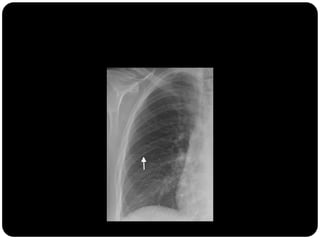

Em que lobo está essa lesão?

Resposta: LID

Importância do

perfil;

Importância da

ausência do sinal da

silhueta;